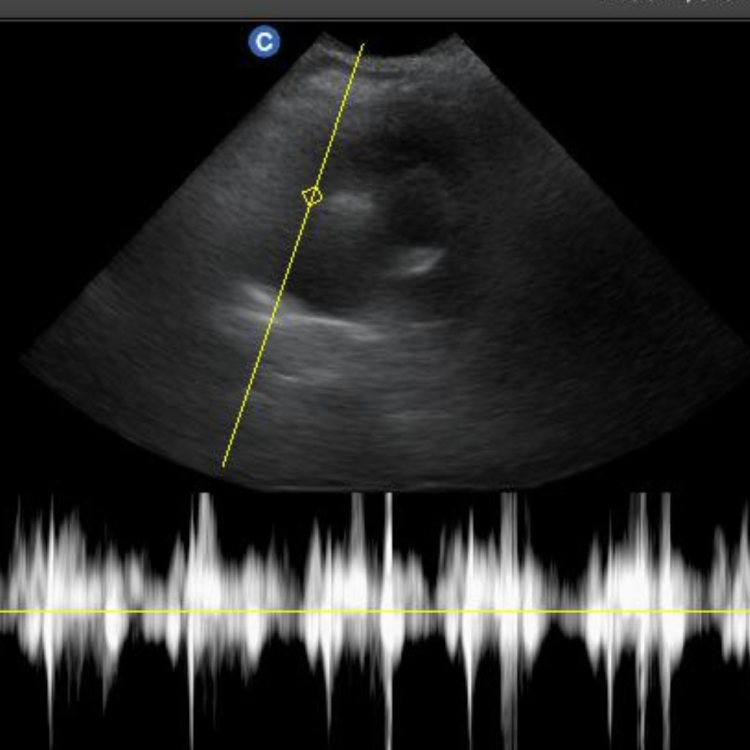

การตรวจอัลตราซาวด์ (Ultrasound) เป็นการตรวจโดยใช้คลื่นความถี่สูงเกินระดับที่หูของคนเราจะได้ยิน การตรวจนี้ค่อนข้างเป็นที่นิยมและใช้กันอย่างกว้างขวาง

สามารถตรวจอวัยวะภายในได้หลายอวัยวะ เช่น หัวใจ หรือ ที่เรียกว่า เอคโคหัวใจ(Echocardiogram) รวมถึงดูอวัยวะในช่องท้องต่างๆ ตับ ม้าม ไต ถุงน้ำดี มดลูก กระเพาะปัสสาวะ รวมไปถึงการดูตัวอ่อนในครรภ์อีกด้วย